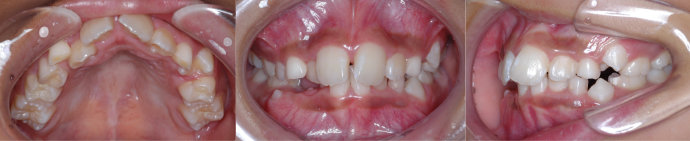

| Case3 |

| 受け口 |

| <治療前> |

| <治療後> |

| 主訴 |

上の歯がねじれている |

| 診断名 |

叢生を伴う反対咬合 |

| 年齢 |

10歳 |

| 使用装置 |

マルチブラケット装置 |

| 抜歯部位 |

永久歯の抜歯は無し |

| 治療期間 |

3年6か月 |

| 治療費概算 |

検査・診断料:5万円+税 装置・技術料:25万円+税 おおよそ1か月ごとの処置・管理料:5,000円+税 保定装置料:5万円+税 |

| リスク・副作用 |

う蝕 |